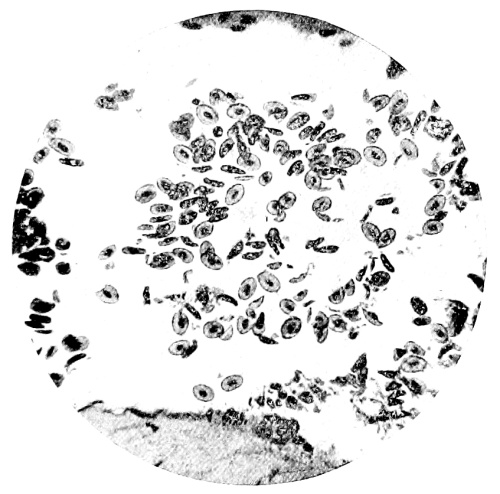

10. Photo-micrograph of Red Blood Corpuscles from Domestic Fowl 99

11. Photo-micrograph of Blood Corpuscles of Fish 99

12. Photo-micrograph of Blood Corpuscles from a Dried Stain of the Blood of a Cod-fish 100

13. Photo-micrograph of a Frog‘s Blood showing oval nucleated Red Corpuscles 101